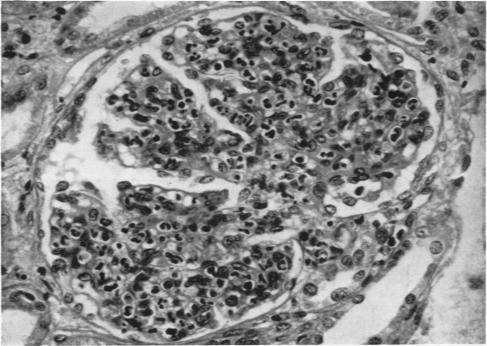

Glomerulonephritis in Africans in Uganda.

Br Med J. 1960 Jun 25;1(5190):1930-8. doi: 10.1136/bmj.1.5190.1930.